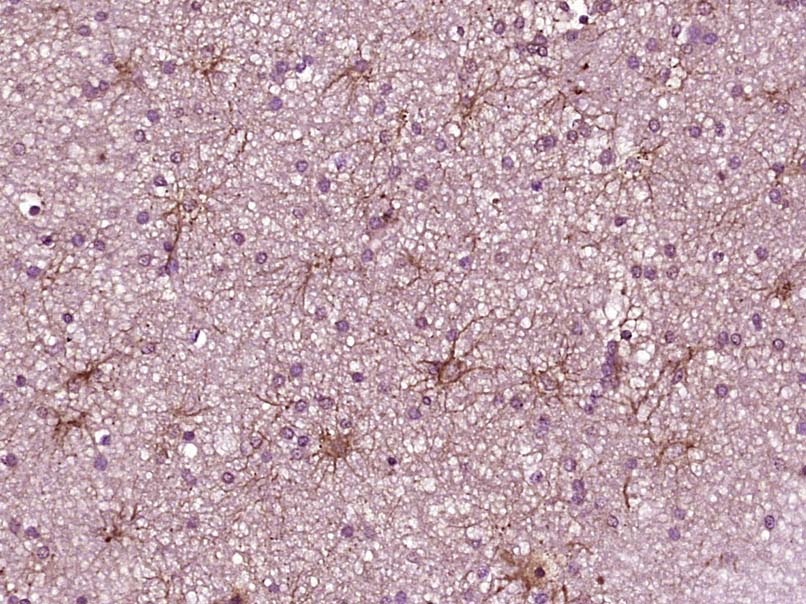

Paraformaldehyde-fixed, paraffin embedded Human liver cancer; Antigen retrieval by boiling in sodium citrate buffer (pH6.0) for 15min; Block endogenous peroxidase by 3% hydrogen peroxide for 20 minutes; Blocking buffer (normal goat serum) at 37°C for 30min; Antibody incubation with _x000D_ JAK1 Monoclonal Antibody, Unconjugated (bsm-33268M) at 1:400 overnight at 4°C, DAB staining.